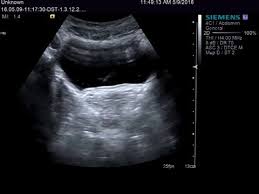

Die Ultraschalluntersuchung Sonografie ist meist die erste bildgebende Untersuchung bei Verdacht auf Blasenkrebs. Die Klassifikation Stadieneinteilung oder Staging genannt ist ein wichtiger Baustein für die Wahl der optimalen Therapie. Dabei kann der Arzt Blase Nieren und Harnwege begutachten.

Eine Ultraschalluntersuchung ermöglicht auch Blasensteine oder einen Blasentumor zu entdecken. Wirken Lymphknoten verdächtig veranlassen Ärzte in der Regel eine Biopsie oder Lymphknotenentnahme. Per Ultraschall lassen sich auch mögliche andere Ursachen für Beschwerden erkennen beispielsweise Nieren- Blasen-. Blasenkrebs kann als Folge einer Strahlentherapie entstehen. Blasenkrebs Mit der Diagnose Blasenkrebs hat der Patient nicht gerechnet. Sofern der Verdacht auf Blasenkrebs besteht nimmt der Arzt eine gründliche Untersuchung vor. Sie stellt zusammen mit der Biopsie Gewebeprobeentnahme die wichtigste Untersuchung für die Diagnose von Blasenkrebs dar. Ziel der Diagnostik ist eine möglichst frühzeitige Diagnosestellung und die Erhärtung oder Ausräumung des Verdachts auf Blasenkrebs. So stellen Ärzte beispielsweise bei Patienten mit einem Gebärmuttertumor ein erhöhtes Risiko für.

Die wichtigste Untersuchung zur Diagnose-Stellung ist die Spiegelung der Harnblase die sogenannte Zystoskopie. Es gibt keine Tumormarker im Blut die spezifisch für Blasenkrebs sind. Per Tastuntersuchung nimmt er dabei die Nierengegend den Unterbauch und die Geschlechtsorgane unter die Lupe. Blasenkrebs Mit der Diagnose Blasenkrebs hat der Patient nicht gerechnet. Liegt ein invasiver Harnblasentumor vor sind tiefgreifende Maßnahmen nötig. Wirken Lymphknoten verdächtig veranlassen Ärzte in der Regel eine Biopsie oder Lymphknotenentnahme. Die Ultraschalluntersuchung Sonografie ist meist die erste bildgebende Untersuchung bei Verdacht auf Blasenkrebs.